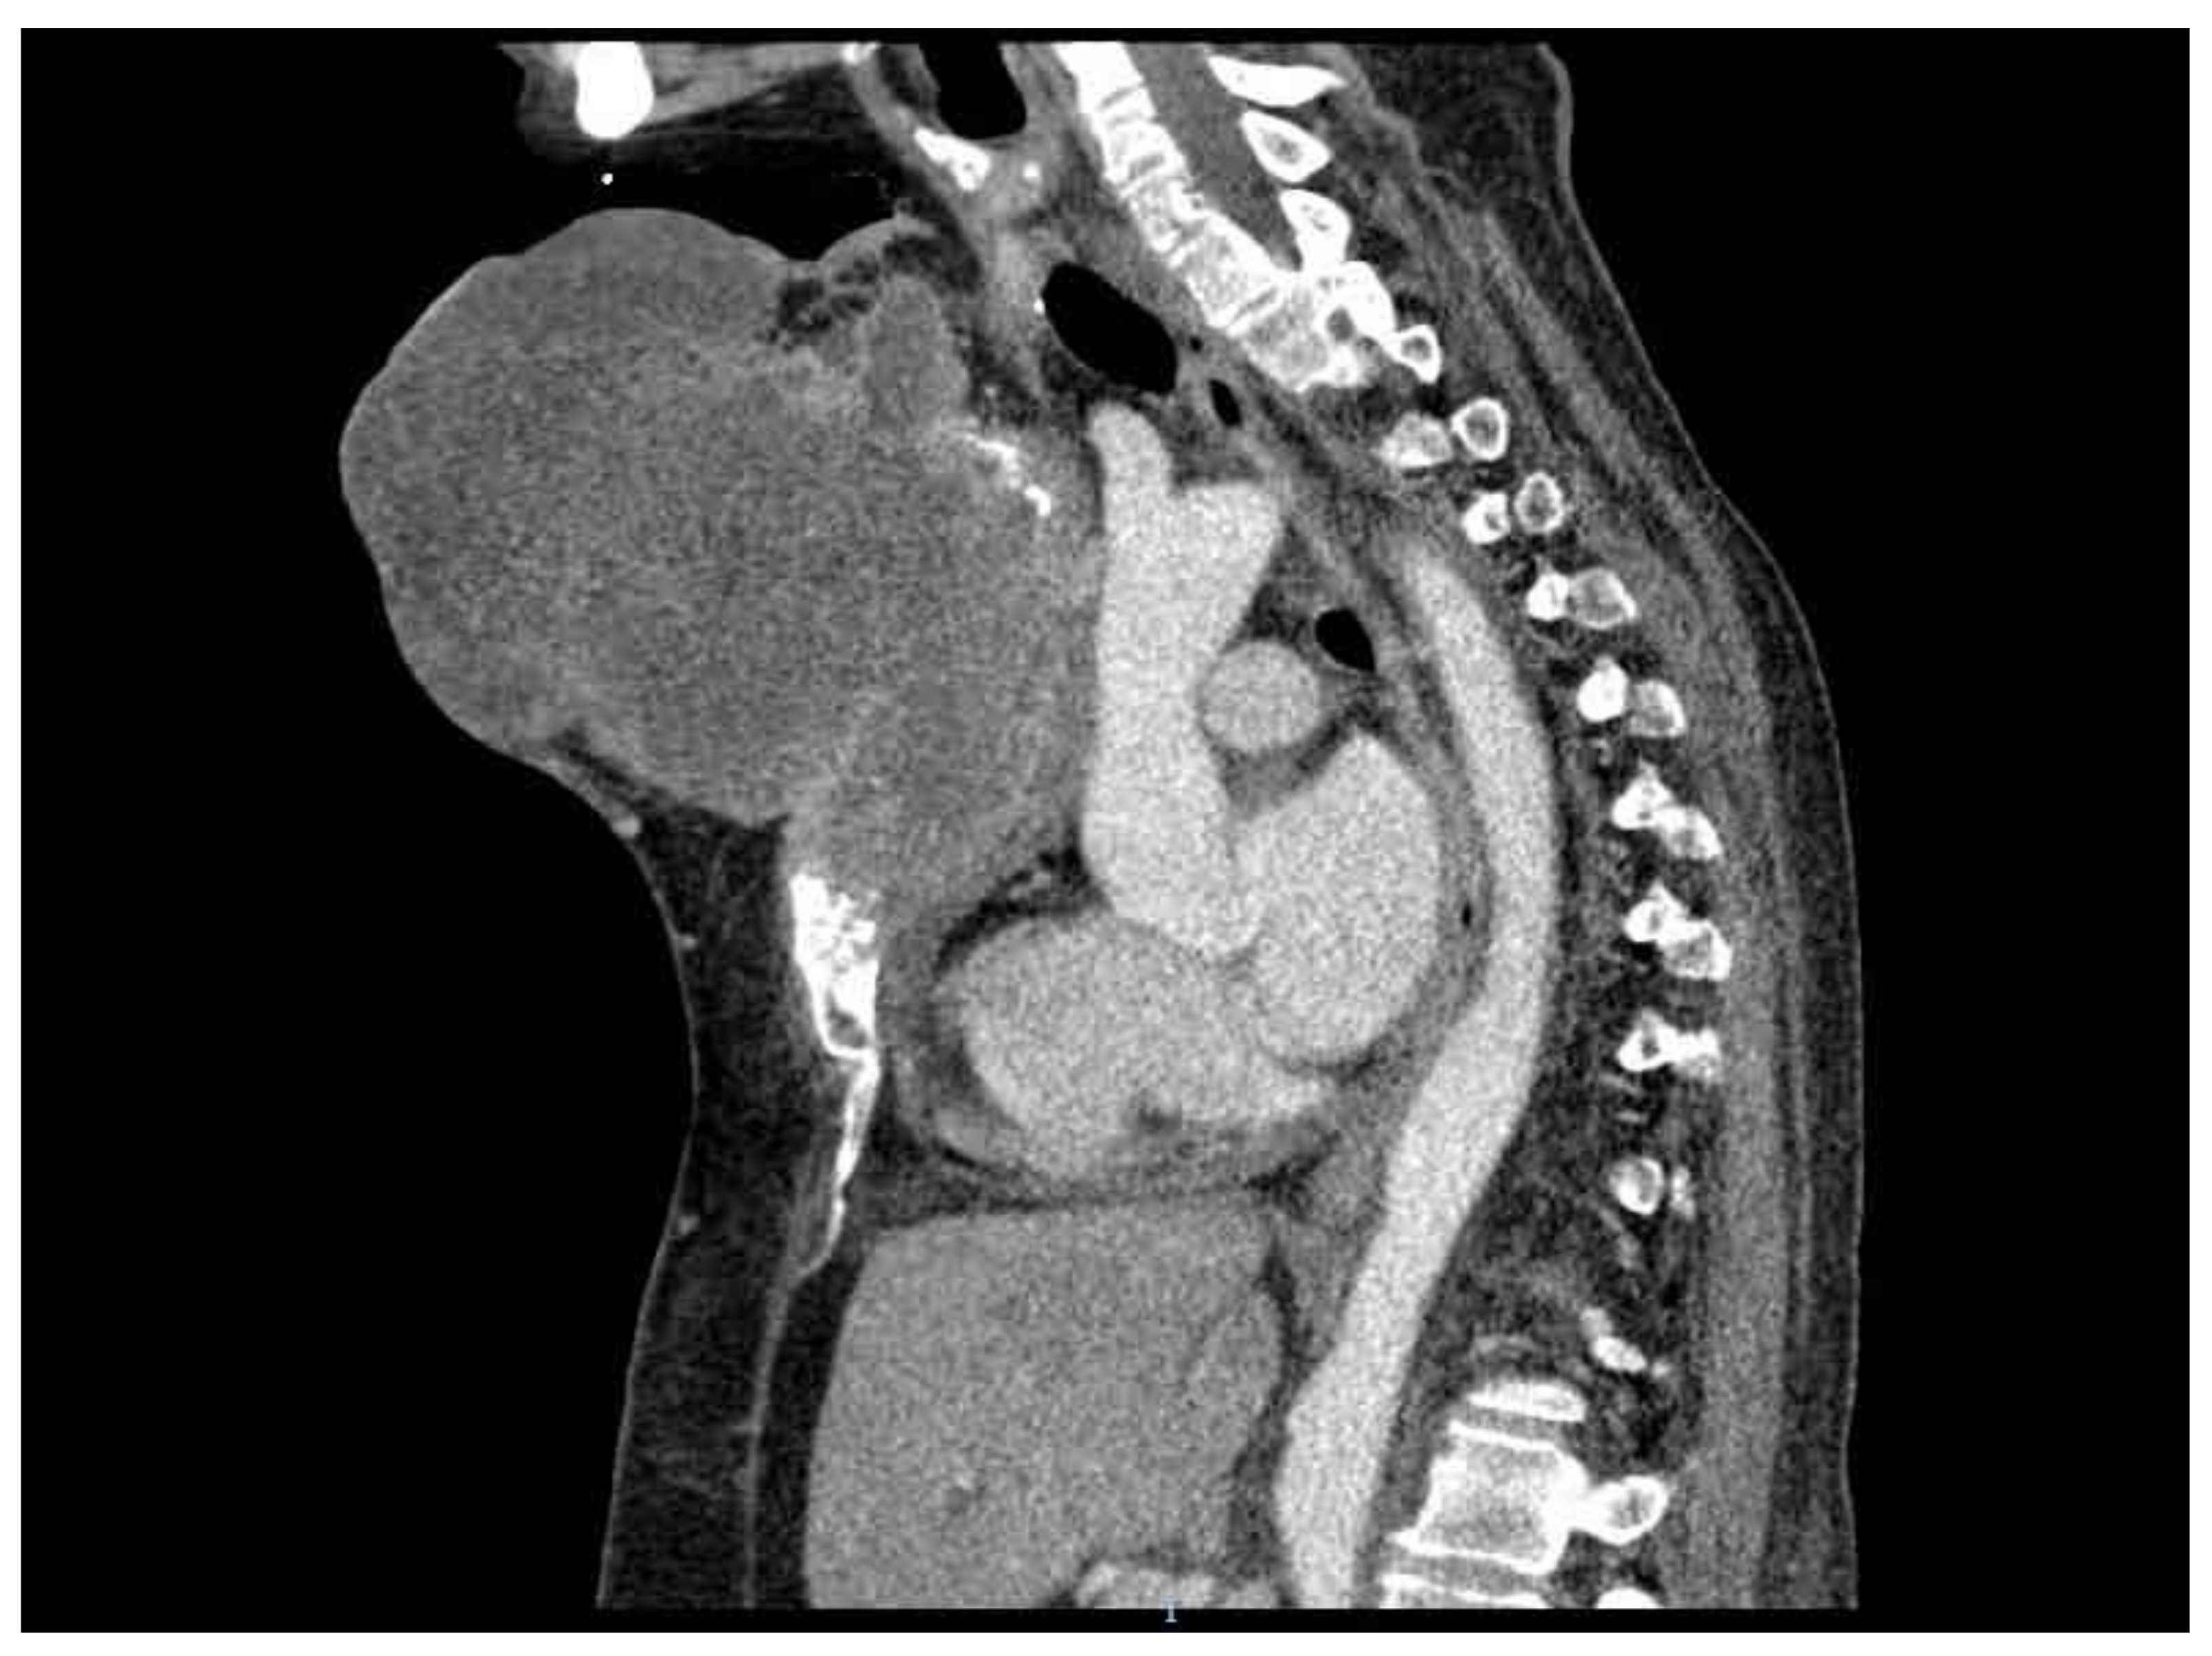

2. Case Presentation